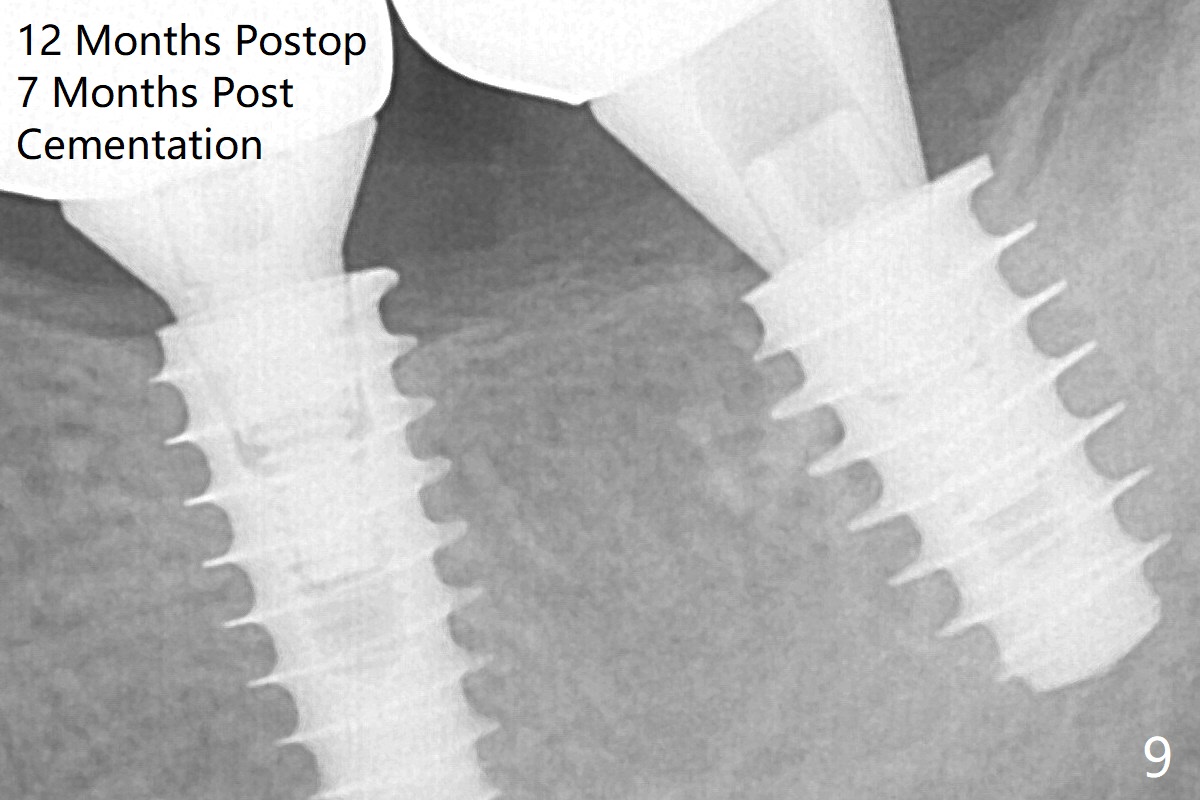

The implant at #19 could be placed more mesially (Fig.4 (*: Vera Graft)).  The implants seem to have osteointegrated 4.5 months postop (Fig.5).  The bony trabeculae form between the 2 implants crestally 12 months postop, i.e., 7 months post cementation (Fig.9).